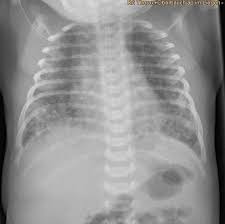

Meconium Aspiration Syndrome Wikipedia

Pharmacotherapy For Meconium Aspiration Journal Of Perinatology

Meconium Aspiration Syndrome You Should Get It Right Iamdrssekandi